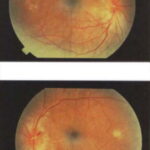

OCULAR DISEASE

Although patients with vitiligo do not usually have ophthalmologic complaints, they can have several ocular findings. Pigmentary abnormalities of the iris and retina may occur. Choroidal abnormalities have been reported in up to 30 percent of patients and iritis in approximately 5 percent. Uveitis can be a frequent ocular manifestation. Exophthalmos may occur in the setting of concomitant Graves disease. Visual acuity is generally not affected.

VOGT-KOYANAGI-HARADA SYNDROME

The Vogt-Koyanagi-Harada syndrome (VKH) consists of vitiligo in association with uveitis, aseptic meningitis, dysacusis, tinnitus, poliosis, and alopecia. It is a rare, systemic, T-cell-mediated autoimmune disorder. VKH syndrome is associated with other autoimmune disorders such as autoimmune polyglandular syndrome, hypothyroidism, Hashimoto thyroiditis, and diabetes mellitus. VKH syndrome classically occurs in three phases. During the first phase, the meningoencephalic phase, patients may have headache, meningismus, seizures, muscle weakness, or paralysis after a prodrome of fever, malaise, nausea and vomiting. Subsequently, the acute ophthalmic phase occurs when patients may develop photophobia, eye pain, and altered visual acuity. Patients may develop uveitis, iridocyclitis, choroiditis, and retinal detachment during this phase and can later develop complications such as cataracts and glaucoma. Vitiligo, alopecia, and poliosis22 usually follow, but can occur before the other manifestations.